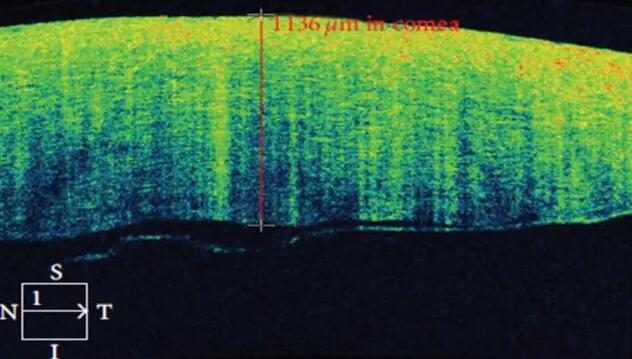

2、角膜厚度评估,角膜水肿、瘢痕、混浊、溃疡、异物、炎症、胬肉等断层观察

3、角膜屈光手术后角膜瓣观察、角膜厚度评估等

4、后弹力层角膜内皮移植术(DSEK)、板层角膜移植术、白内障术后内皮层脱落等术后观察